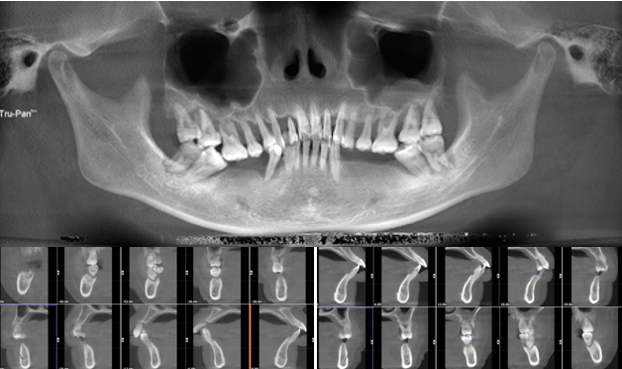

· 双侧髁突骨皮质连续。

· 修复体戴入后髁突位于关节窝内的适中位置。